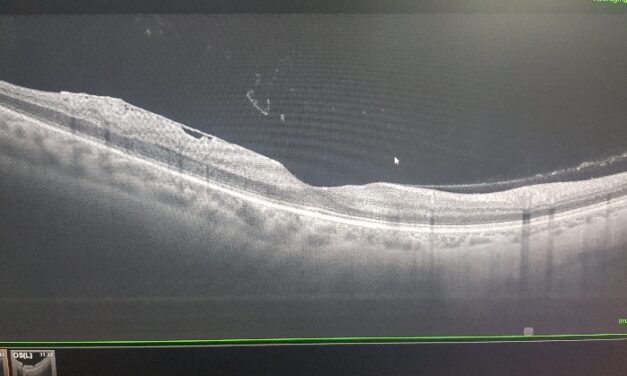

Per saperne di più08/09/2014 | Retina Vitreo Maculopatie

Cosa sono i corpi mobili del vitreo e le miodesopsie (floaters)Cause di miodesopsie e cause di...